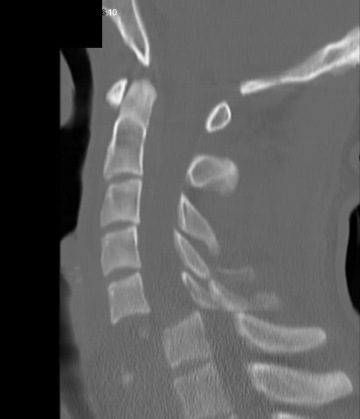

Pro vaši informovanost bych ještě rád zmínil mechanismus vzniku úrazu. Pokud je skákaná tzv. šipka, je prvním tvrdším letícím předmětem o vysoké kinetické energii hlava. Poté následuje krční páteř a dále opět část těla s vyšší tuhostí, tedy hrudní koš, následovaný břichem a dolními končetinami. Veškerá decelerační energie vznikající nárazem hlavy na překážku (dno) se tedy koncentruje na místo nejmenšího odporu, tedy krční páteř (samozřejmě nelze vyloučit, že je při skoku poraněna i hlava nebo hrudní páteř). Dochází k rozlomení obratle (nejčastěji C5, nebo C6 a C7) s tlakem úlomku do páteřního kanálu a poškození míchy.